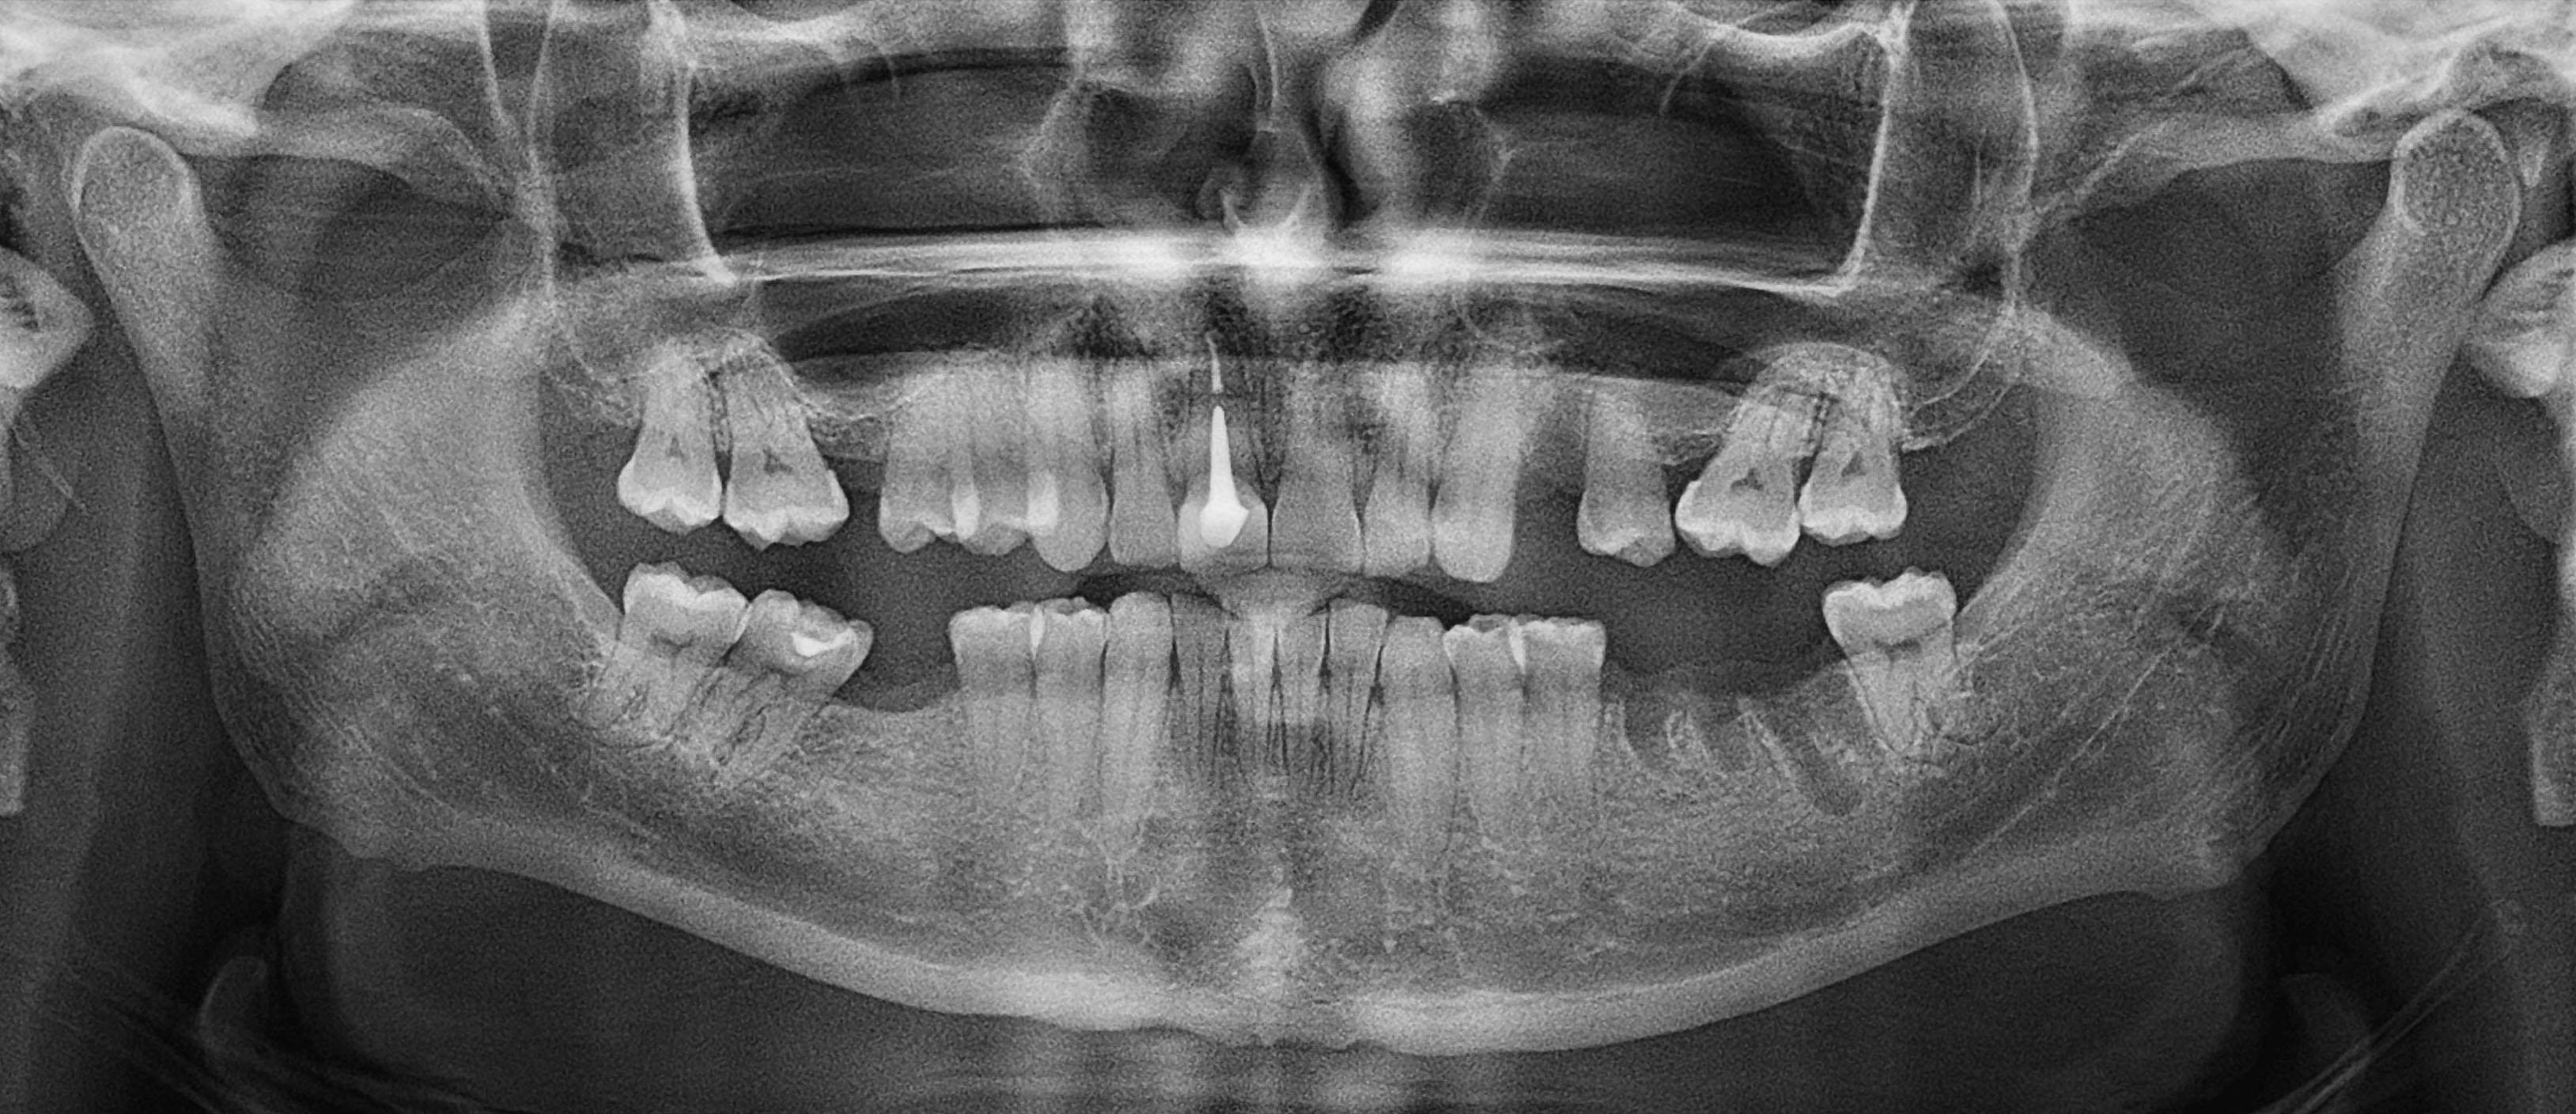

Ортопантомограма (ОПТГ)

Тип знімку - 2D

Вартість - 450 CZK

Загальний час прийому - 15 хв

Час сканування - 10 сек

Друк на фотопапері / e-mail / лікарю на ftp